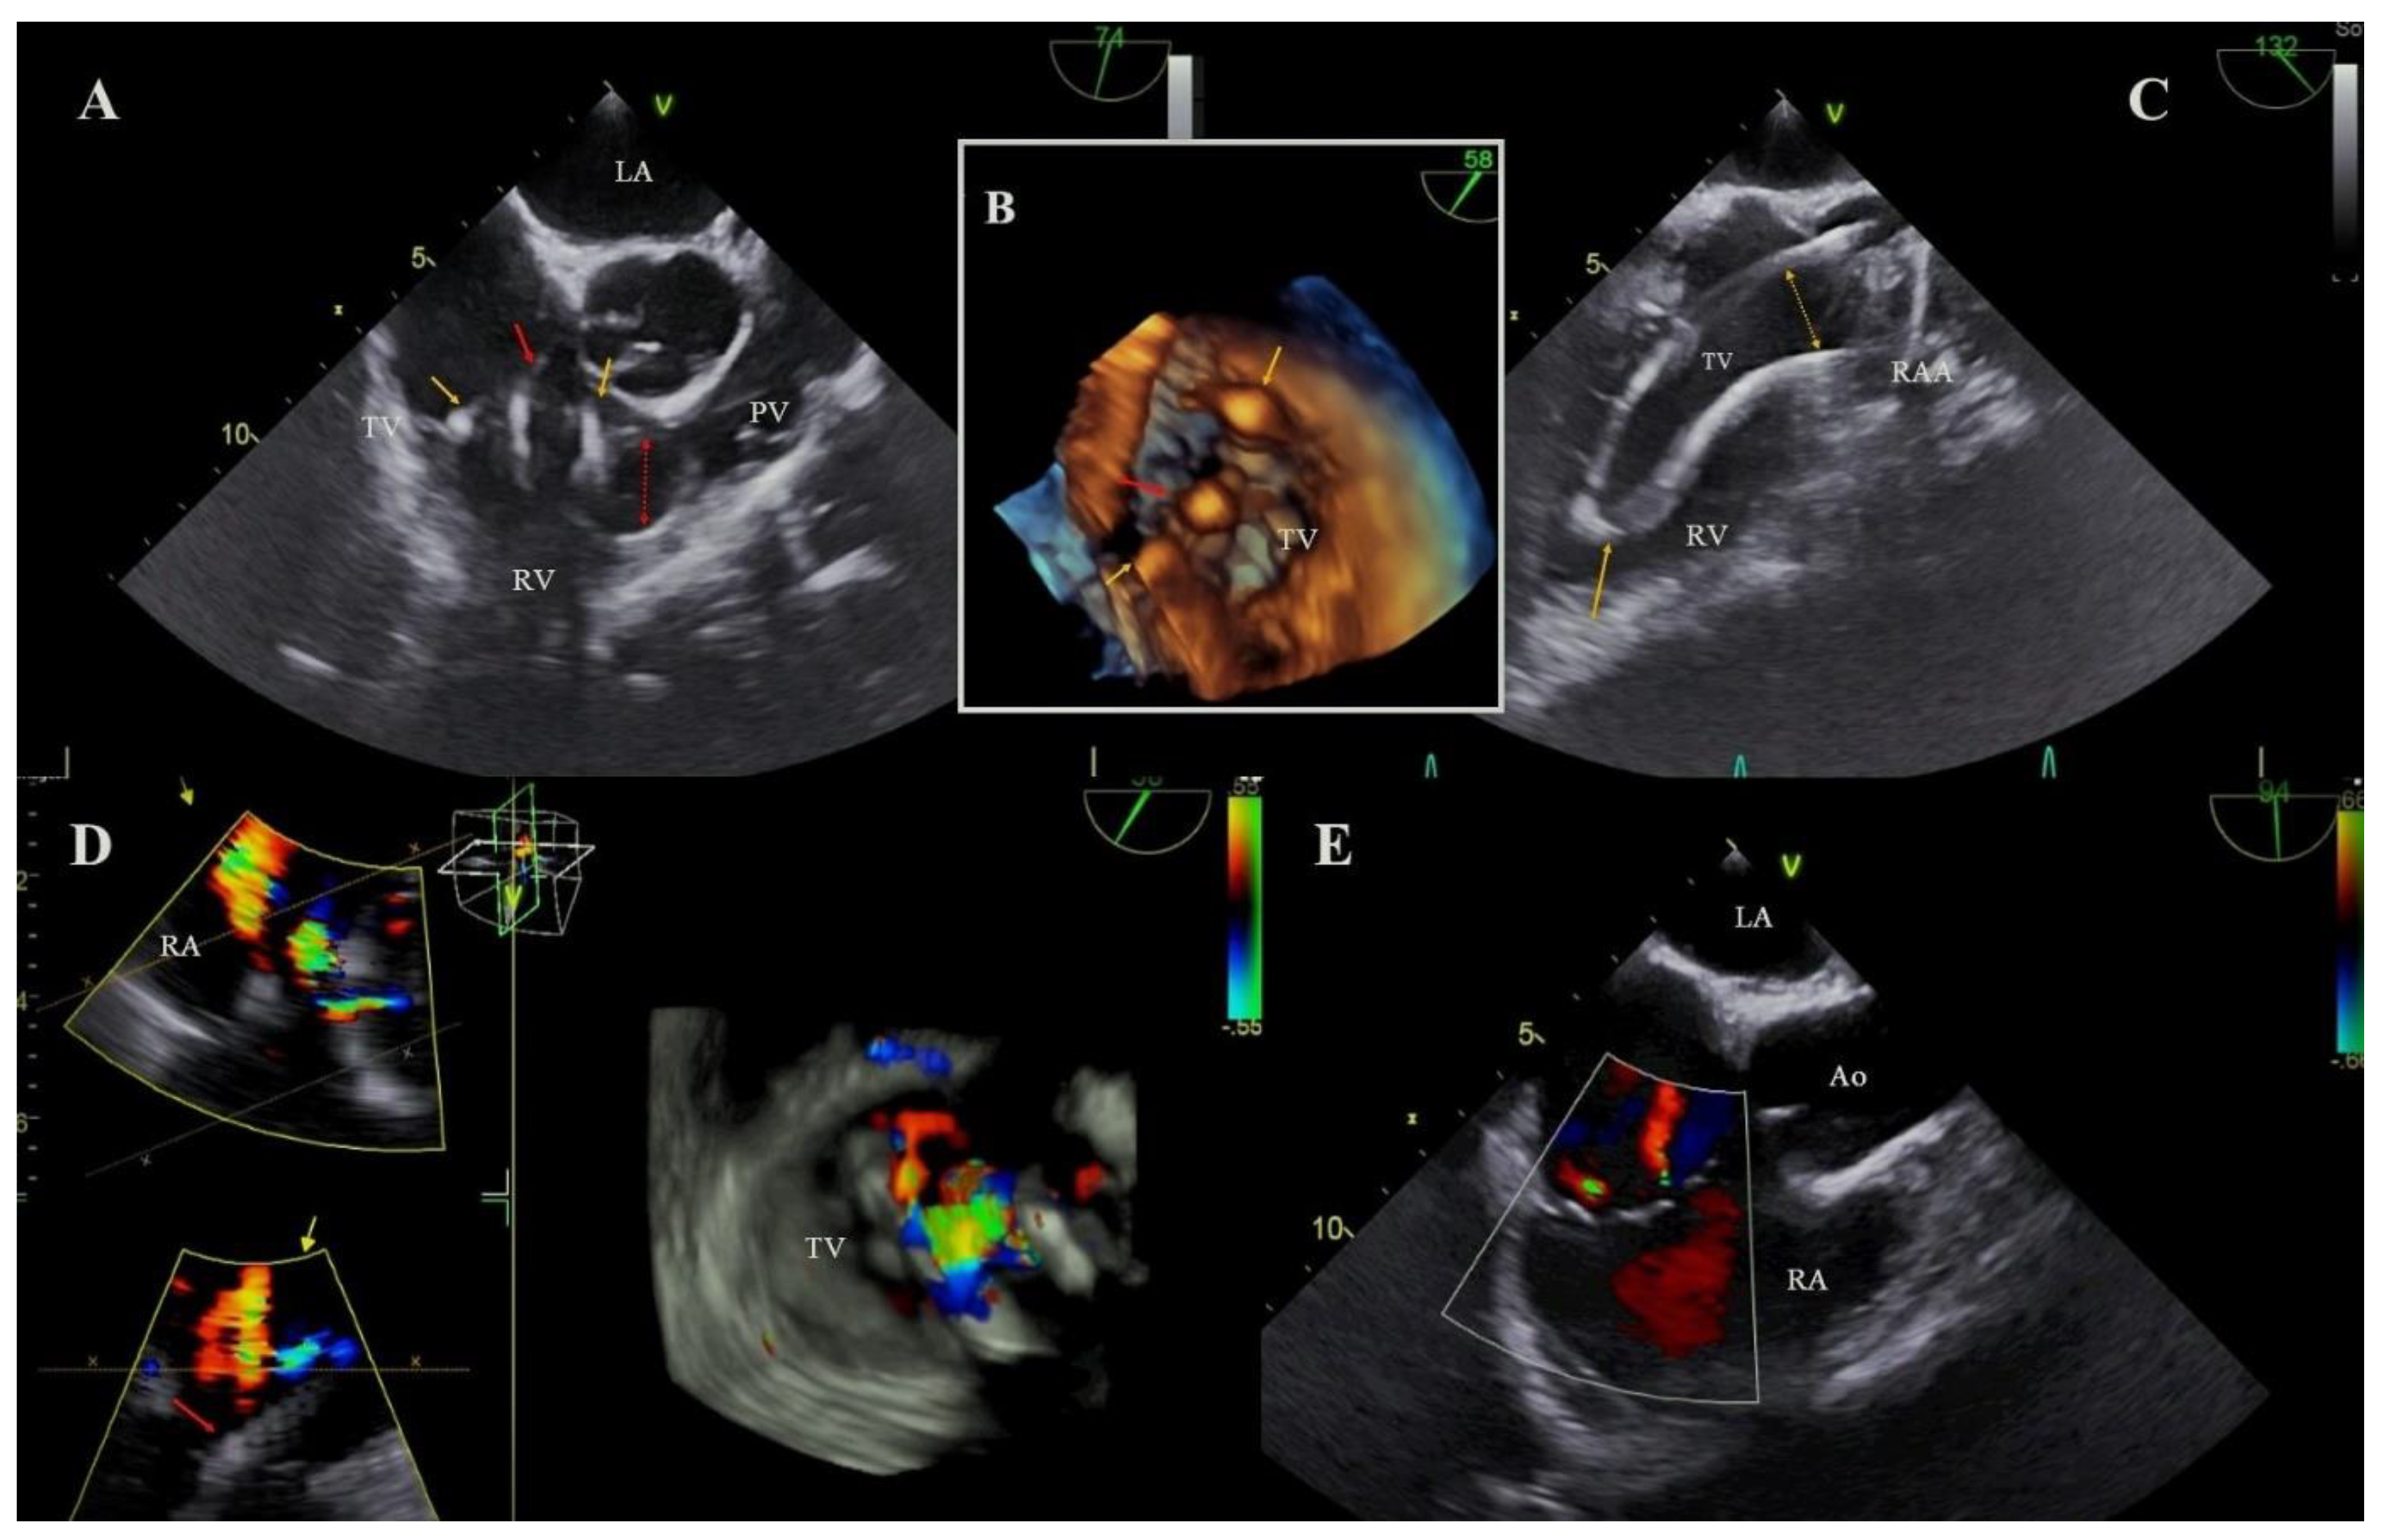

:1. Introduction

2.3. Echocardiography